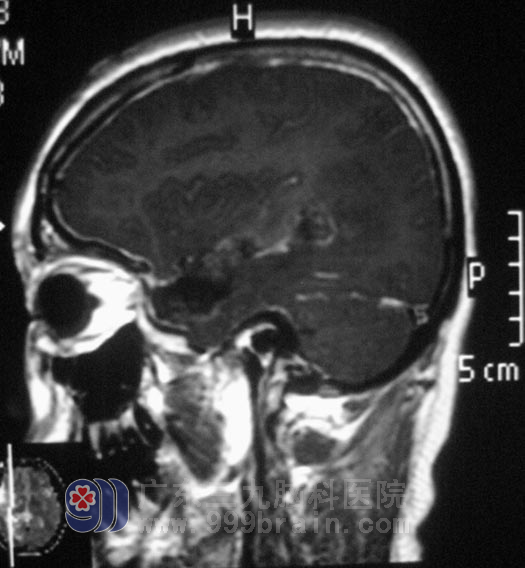

由于陈女士的病变部位主要是位于功能区,4月12日,由鲁明主任主刀,在唤醒麻醉+电生理监测下行右侧颞枕叶多发占位切除术+右侧颞极切除术,术中导航定位右侧颞叶顶部肿瘤位置,避开功能区,镜下见右侧颞肌脑组织呈肉芽组织增生样改变。手术在陈女士保持说话及肢体运动中进行,切除增生肉芽组织,见一类似寄生虫长条形物质存在,取出后未见明显活动,予适当扩大切除病变脑组织及肉芽肿。术后陈女士的语言及肢体运动均没有受到影响。术后病理结果为:符合虫体(裂头蚴)所致肉芽肿性炎。

▲手术后